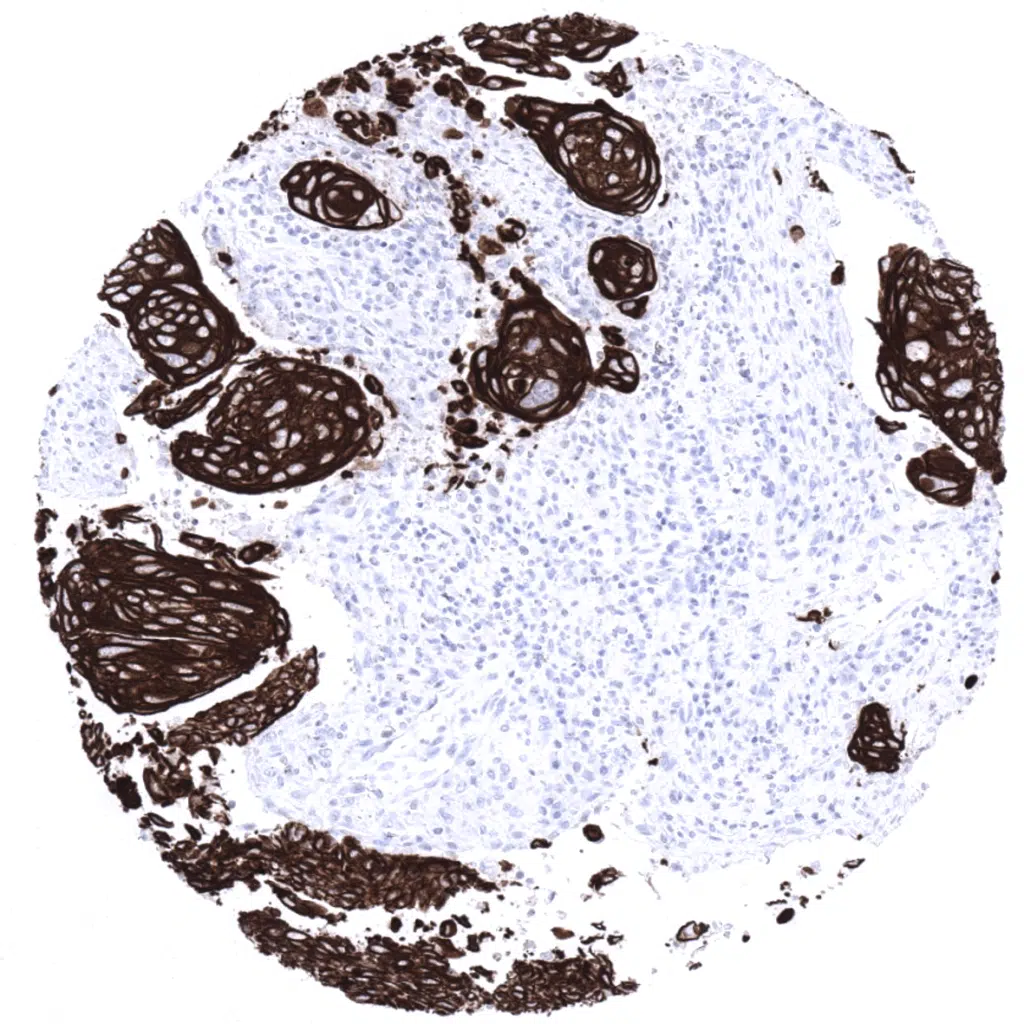

Poorly differentiated cervical squamous cell carcinoma with strong Cytokeratin 5 immunostaining.